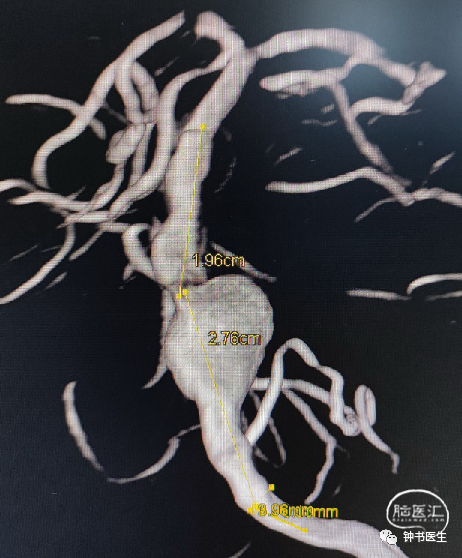

椎基底夹层动脉瘤:65Y M,脑干梗塞

术后患者无明显不适(TB 6.0X45)